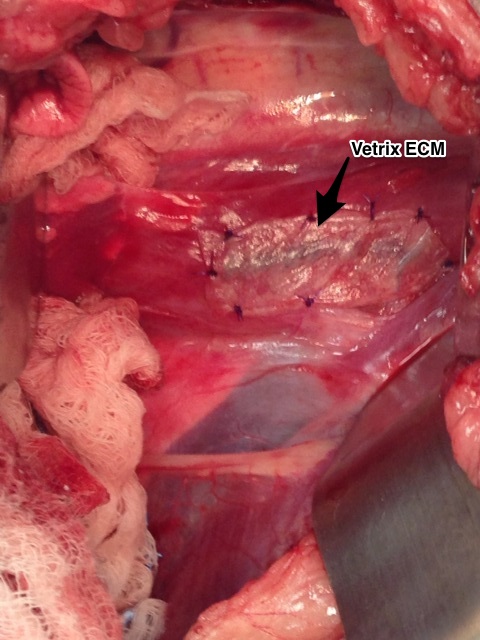

The standard treatment for a primary lung tumor is surgical removal. At this juncture (or earlier) your primary veterinarian may recommend that you consult with a board certified veterinary surgeon due to the intricacy of the procedure and the “around the clock” care your family member will require following surgery (if your veterinarian does not offer this service). Generally, surgical removal of the tumor is the standard of care for treatment of this disease. Smaller tumors can sometimes be removed by thoracoscopy (minimally invasive scoping of the chest), however a very experienced anesthesia team is need to provide one lung lobe ventilation to the pet. Usually the tumor is accessed by a lateral thoracotomy depending on the which side of the chest the tumor is located. The tumor is isolated and the affected lung lobe is removed (various techniques can be used). I prefer removal with a Thoracoabdominal (TA) stapling device. In all surgeries, a chest tube is placed for 12-24 hours following surgery.